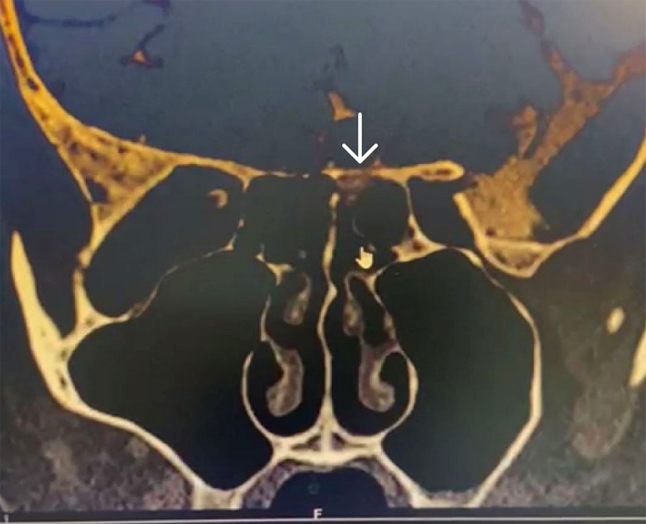

CT cisternography revealed thinning and erosion of the left cribriform plate posterior to the crista galli (figure 1) and the lateral recess of the left sphenoid (figure 2).

Figure 1. CT cisternography -arrow showing thinning and erosion of the left cribriform plate posterior to the crista galli showing csf leakage